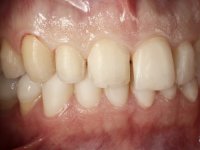

Realizado o diagnóstico e tomada a decisão quanto ao tratamento a executar, tornou-se importante definir qual a sequência de trabalho a adotar no sentido de conseguir a reabilitação da D.V.O. (V.D.O), de forma progressiva e equilibrada. Na primeira fase fez-se uma pré-impressão da arcada inferior com silicone tipo “putty” e em seguida realizou-se o preparo dentário de todo o sector posterior. O preparo para os overlays foi feito coronalmente à linha amelo cementaria no sentido de ser o mais conservador possível. A impressão foi feita com técnica de dupla mistura após afastamento gengival realizado com pasta de caulino. A provisória foi realizada com resina composta de polimerização dual. Em laboratório foram realizados os overlays após se ter aberto ligeiramente (1,5mm) a D.V.O. nos modelos montados em articulador semi-ajustável. Simultaneamente o sector antero-inferior foi encerado no sentido de acompanhar este aumento da D.V.O. Também foi confecionada uma chave de silicone translucido para posterior confeção dos provisórios antero-inferiores. Em boca foi primeiro realizada a provisionalização dos dentes anteriores utilizando resina composta previamente aquecida após preparação das superfícies dentárias para a adesão. Foi colocado o dique de borracha para promover o isolamento absoluto e posteriormente foram colados os overlays. Em laboratório foi realizada nova chave de silicone para confecionar os provisórios antero-superiores. Seguidamente em boca foram preparados os seis dentes antero-superiores após colocação do fio de afastamento gengival. Feita a preparação adequada das superfícies dentárias foi realizada a impressão com técnica de dupla mistura e a respetiva provisória. Em laboratório foram confecionadas 6 facetas feldespáticas num modelo de trabalho tipo “Geller”. A provisória foi removida e as facetas foram coladas em boca utilizando um isolamento relativo competente. Esta opção foi tomada em virtude de uma prévia experiencia negativa com a colocação do dique de borracha na mandibula. Após a colagem dos laminados antero-superiores foram dadas 12 semanas para avaliar a adaptação do paciente à nova situação e então iniciar a confeção das facetas antero-inferiores. Após colocação do fio de afastamento gengival. foram feitos os preparos dentários adequados e em seguida foi feita a impressão. Também foi feita a preparação do dente 3.4 que, entretanto, tinha sofrido uma fratura do overlay. As facetas e a restauração do 3.4 foram realizadas num modelo de trabalho tipo “Geller”. Após remoção da provisória, as facetas foram coladas em boca, utilizando um isolamento relativo pelas razões apontadas anteriormente. Após colocação do trabalho o paciente foi reabilitado por outros colegas com um implante na zona do 2.6 e substituição da coroa aparafusada sobre o implante colocado no local do 3.5. Posteriormente surgiram fraturas nos overlays dos dentes 4.7 e 3.7 que foram reabilitados com overlays em Zr.